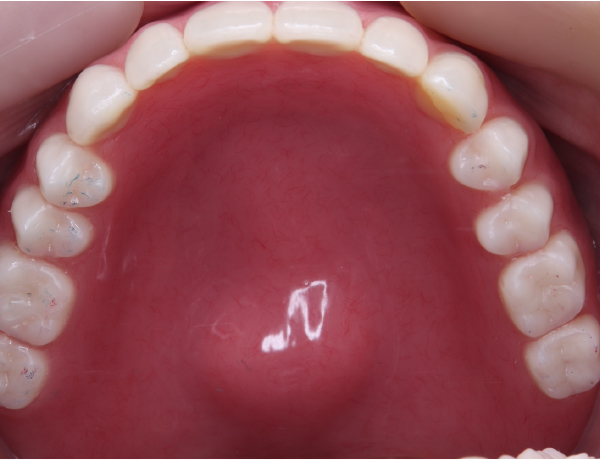

上あご

赤丸の部分にこれでもかってくらい大きな骨の隆起があります。噛む力がかなり強そうです。

1. 噛む力が非常に強い お口の中には骨隆起が認められました。赤丸で示している部分が、口蓋隆起と呼ばれる骨の盛り上がりです。このような骨隆起がある場合、噛む力が一点に集中しやすく、入れ歯に通常以上の負担がかかります。

患者さんのかみ合わせやかむ力を考慮して、金属の入れ歯を選択しました。写真を見ると分かると思いますが、入れ歯の金属の部分がとにかく大きく広くとってあります。この金属の設計は、先代の田中久敏に習ったデザインになりますが、口蓋の吸収しない部分は、金属で出来るだけ広く覆って、それ以外の部分は、ピンクのレジンで覆っています。

お口の中に入っても、金属の部分がだいぶ広くとってあるのが分かるかと思います。口蓋隆起と言われる骨の部分が当たると痛みが出るので、少しその部分はリリーフして隙間を与える工夫もしています。